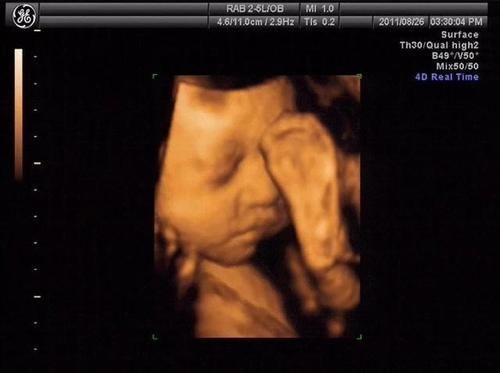

【 彩超|做四维医生说腹部脂肪厚,看不清,打出来单子也只能看宝宝大概面部怎么办?】一.彩超看胎儿的原理是什么?我们通常看胎儿使用二维彩超就可以了,这种彩超技术看胎儿的原理就是把所见到的影像形成一个切面,呈现出一个平面展现出来,非常直观,胎儿主要看胎儿的四肢和身体结构使用二维彩超即可以看见。现在的二维彩超在平面技术的基础上加上了血流信号的显示,就是我们经常去做的多普勒超声检查,在妇产科主要看胎儿脐血流,心脏血流情况,通过血流信号可以判断胎儿血流供应情况。

二.肚皮太厚,胎儿看不清怎么办?肚皮的厚度就像墙壁一样,超声的原理就是声波的穿透性,如果肚皮越厚,也声波越难以通过,在彩超机器上就难以显示出来。如果你看的是羊水量,脐血流其实影响不大,因为血流信号一般都能显示出来;如果看的是胎儿身体结构,则肚皮厚度超过5cm以上的孕妇则很难看清。此时磁共振是解决肚皮厚照不到胎儿的有效解决办法。